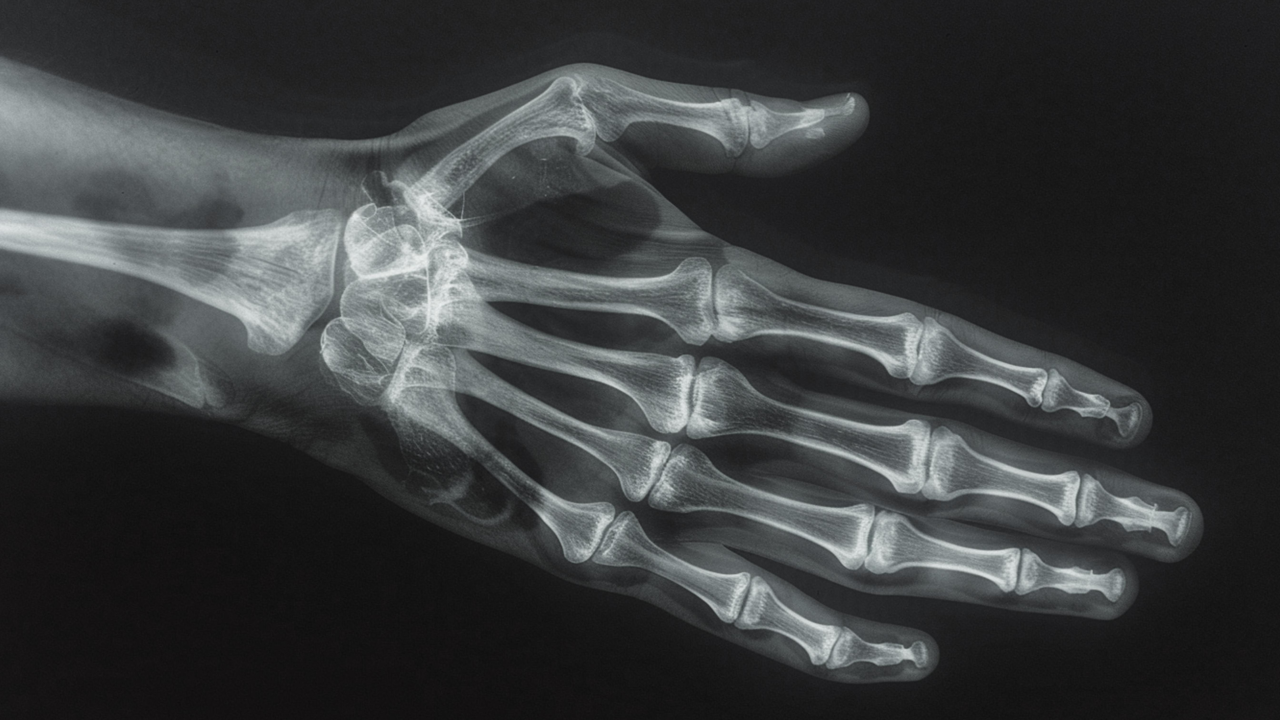

골관절염은 무릎뿐만 아니라 척추, 엉덩이 관절, 손가락 마디에서도 흔하게 발생하는데요.

손가락 골관절염: 중년 여성에게 많이 발생하며 손가락 마디가 서서히 굵어지고 아침에 뻣뻣함을 느낌